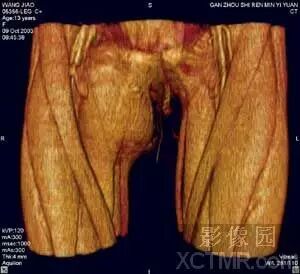

2)血管系统

VR作为MS-CTA的主要后处理技术在血管系统特别是对动脉血管系统病变要以清晰、确切地显示大范围复杂血管的完整形态、走行和病变,图像立体感强,能以多角度直观地显示病变与血管、血管之间以及血管与周围其它器官之间的三维空间解剖关系,其诊断价值已经被临床医生认可。对大动脉血管病变如:动脉瘤、动静脉畸形、狭窄、梗塞、闭塞、夹层和血管壁的钙化等的诊断已经基本取代了DSA检查。对脑动脉瘤的诊断国、内外有关研究报告证实3D-CTA具有很高的准确性、敏感性和特异性,可以确切地检出瘤体直径<3mm的脑动脉瘤。作为一种快速和非创伤性检查手段,可以准确地显示瘤体的位置、形态和大小,评价瘤颈部与瘤体、载瘤动脉和周围血管之间的空间关系,模拟手术入路为选择适当的手术治疗方案提供直观、可靠的依据,可以作为脑动脉瘤的首选影像学诊断方法。近年来,有许多文献报道主张用3D-CTA取代或部分取代DSA诊断脑动脉瘤。

VR在泌尿系统疾病的检查中,可以通过去骨、剪切、旋转来显示肾盂、输尿管、膀胱,也可以保留脊椎、骨盆,也可以将泌尿系统的器官和骨骼用不同的颜色区别开。肿瘤应用VR多曲线调整(Free setting Multi-Threshold values Curve)技术可以将经对比剂强化的各系统和器官的肿瘤在同一幅三维图像上同时获得骨、血管和软组织的影像,能够对肿瘤准确地定位、完整地显示病灶本身的状态以及与周围组织器官和血管的毗邻关系和受侵及、挤压移位等情况。经处理后的图像可以对病变进行任意角度的旋转,多方位观察和分析。为了清晰地显示病灶的隐蔽部分,可对图像进行剪裁、切割、钻洞和制作自动电影,为临床医生对疾病做出正确的判断提供更加丰富的影像学信息。